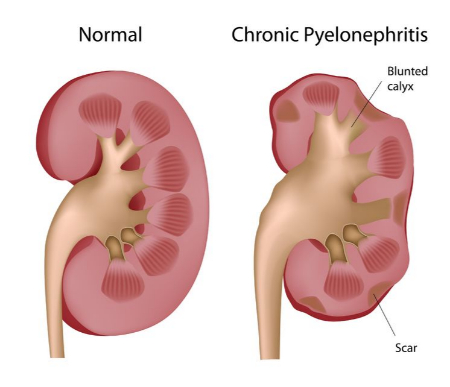

در موارد مزمن، انسداد طولانیمدت میتواند عفونتهای ادراری را تشدید کند، با علائمی مانند:

آیا استاز کلیه خطرناک است؟

استاز و ورم کلیه در صورت عدم درمان میتوانند خطرناک باشند. انسداد طولانیمدت ممکن است باعث آسیب دائمی به بافت کلیه شود، که در موارد شدید به نارسایی کلیه، نیاز به دیالیز یا حتی پیوند کلیه منجر میشود. تشخیص و درمان زودهنگام برای جلوگیری از این عوارض حیاتی است.